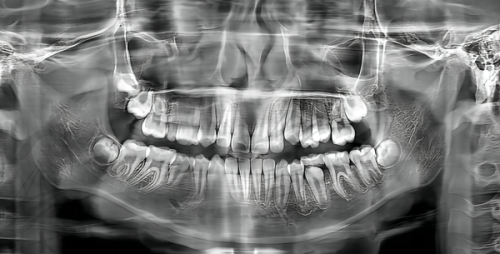

种植牙是特别多牙齿缺失患者关注的项目,而郑州南区口腔医院在种植牙方面有着诸多优势。首先从设备方面来看,医院拥有精良的医疗器材。例如超声骨刀,在手术过程中不使用凿子和锤子,相较于传统拔牙方式,它具有创伤小、感染机会少、愈合快等优点。患者在使用超声骨刀进行拔牙或种植相关操作时,能减少痛苦,更快地修复健康。此外,医院还引进了芬兰口腔CT,它可以更好地获得口腔数据,医生能够根据这些精细的数据为患者制定更符合自身口腔情况的方案,大大提高了种植牙的成功几率和成效。

李先生是一位牙齿缺失多年的患者,之前一直因为害怕手术痛苦和担心成效而不敢进行种植牙。后来在朋友的推荐下来到了郑州南区口腔医院。医生为他进行了详细的检查,利用芬兰口腔CT获取了精细的口腔数据,并制定了个性化的种植方案。在手术过程中,使用了超声骨刀,李先生说整个过程并没有想象中的那么痛苦,术后修复也特别快。现在,李先生已经成功种上了牙齿,能够正常饮食,生活质量得到了较大的提高。